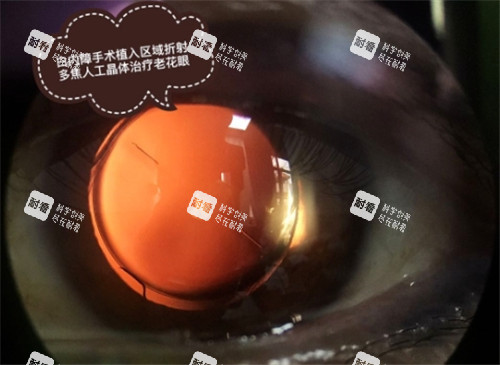

通过手术摘除混浊的晶状体,并植入人工晶状体,可以有效改善患者的视力。

除了基础款手术,白内障手术中人工晶状体的选择也会对手术价格产生较大影响。

其中,三焦点晶体是一种比较靠前的人工晶状体,价格在2.2万左右。

三焦点晶体具有独特的光学设计,可以同时提供远、中、近三个焦点的清晰视力。

这意味着患者在植入三焦点晶体后,无论是看远处的风景、中间距离的电脑屏幕,还是近处的书本,都能获得清晰的视觉结果,大大提高了生活质量。